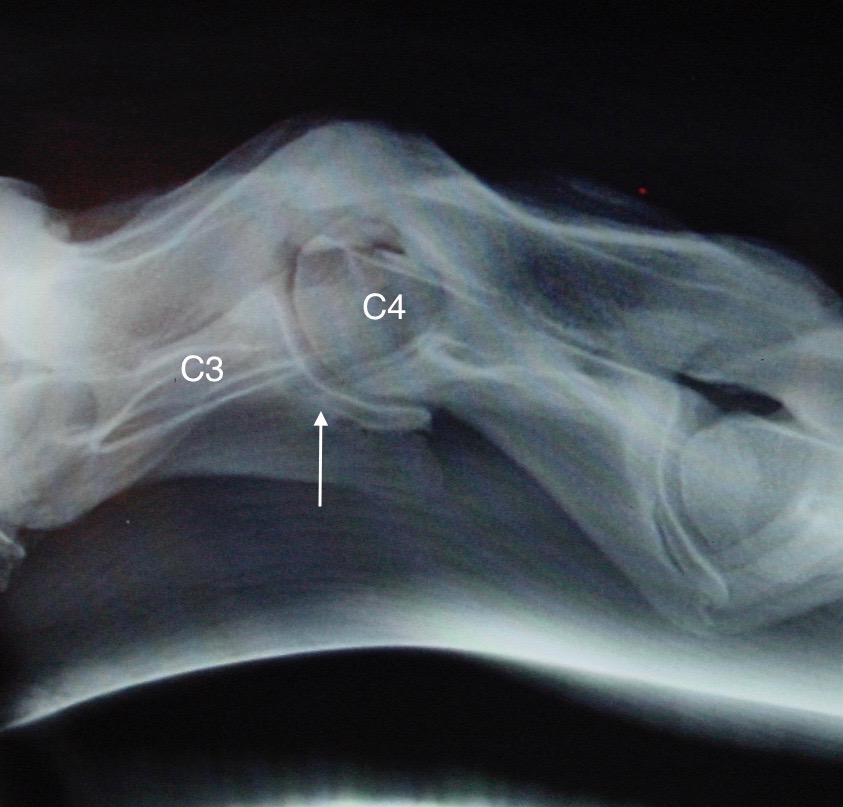

Další krok v diagnostice problémů krku je zhotovení rentgenových snímků celé krční páteře (od lebky po první hrudní obratel). Toto vyšetření může odhalit četné abnormality, například zúžení páteřního kanálu, subluxaci obratlů (obr. 3), závažnou artrózu nebo zlomeniny.

Obrázek 3: Závažná subluxace C3–C4